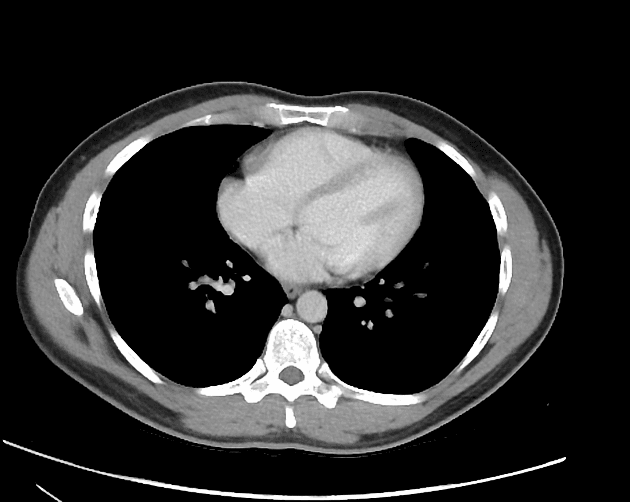

Chụp CT định kỳ ban đầu

Chụp CT có tiêm thuốc cản quang (pha tĩnh mạch cửa) cho thấy các hình ảnh sau:

Có tắc hoàn toàn thân chính đoạn xa của động mạch mạc treo tràng trên và các nhánh của nó, ngoại trừ các nhánh ruột non gần bên trái và động mạch đại tràng giữa bên phải. Các nhánh ruột non xa, nhánh hồi tràng, động mạch hồi – đại tràng và động mạch đại tràng phải đều bị tắc.

Trong trường hợp này, chúng ta cần lưu ý rằng các thay đổi ở ruột trong thiếu máu cục bộ động mạch rất tinh tế và dễ bị bỏ sót: thành ruột không dày lên mà thậm chí còn mỏng đi, và khí trong thành ruột (pneumatosis) rất mờ nhạt. Ngoài ra, cần chú ý rằng mô mỡ mạc treo rất rõ ràng. Điều này hoàn toàn khác biệt với thiếu máu cục bộ tĩnh mạch, trong đó có dày thành ruột rõ rệt, xuất huyết nội thành, và mô mỡ mạc treo bị phù nề mờ đi.